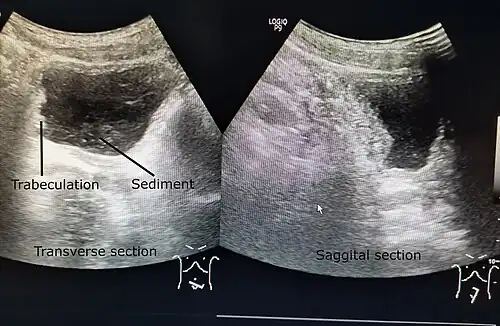

| A paraplegic patient with neurogenic bladder on regular ultrasound follow-up showing thickened bladder wall with trabeculations and sediments within the bladder. | |

Ultrasound imaging can give information on the shape of the bladder, post-void residual volume, and evidence of kidney damage such as kidney size, thickness or ureteral dilation.[12] Trabeculated bladder on ultrasound indicates high risk of developing urinary tract abnormalities such as hydronephrosis and stones.[13] A voiding cystourethrography study uses contrast dye to obtain images of the bladder both when it is full and after urination which can show changes in bladder shape consistent with neurogenic bladder.[12]